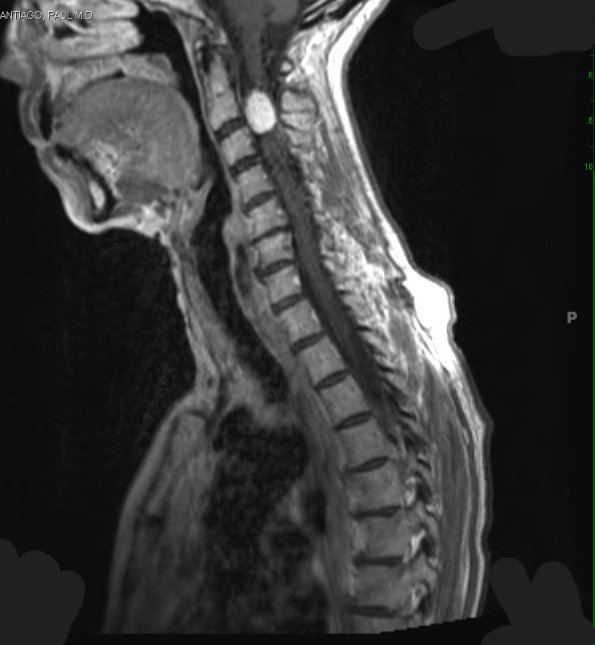

A T1-weighted image with contrast shows the spinal tumor.